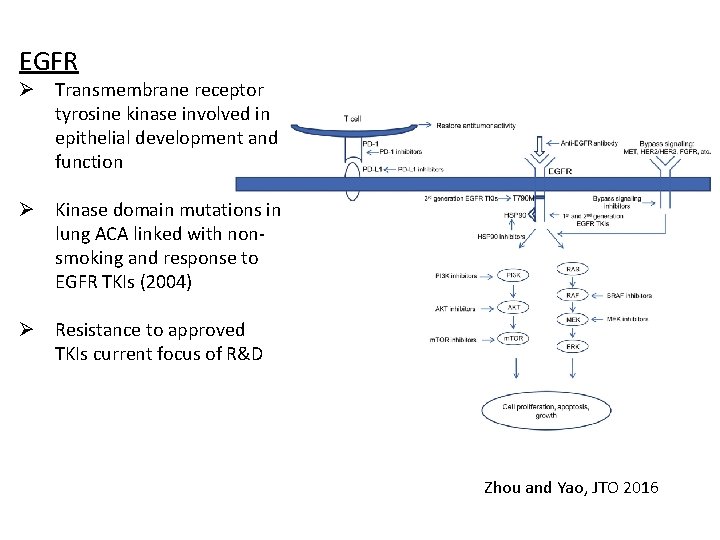

EGFR Ø Transmembrane receptor tyrosine kinase involved in epithelial development and function Ø Kinase domain mutations in lung ACA linked with nonsmoking and response to EGFR TKIs (2004) Ø Resistance to approved TKIs current focus of R&D Zhou and Yao, JTO 2016